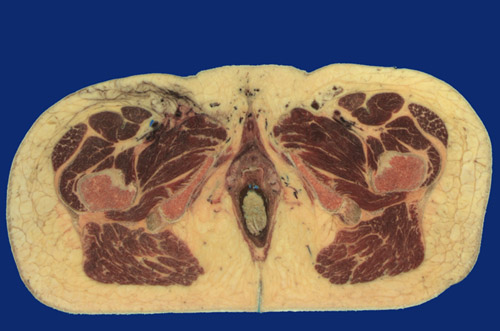

Identify the following regions in the image above: Ischiocavernosus m. - Bulbospongiosus m. - Crus of clitoris - Vagina - Urethra - Bulb of vestibule (corpus spongiosum) - Great saphenous vein - Femoral artery & vein - Sartorius - Rectus femoris - Vastus intermedius - Tensor fasciae latae - Vastus lateralis - Quadratus femoris - Gluteus maximus - Adductor magnus - Femur - Ischium - Ischioanal fossa - Rectum - Levator ani